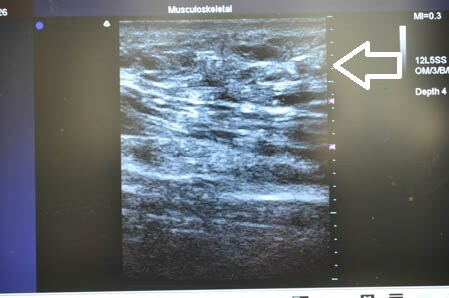

左も同様に見てみましょう。

↓ ↓ ↓